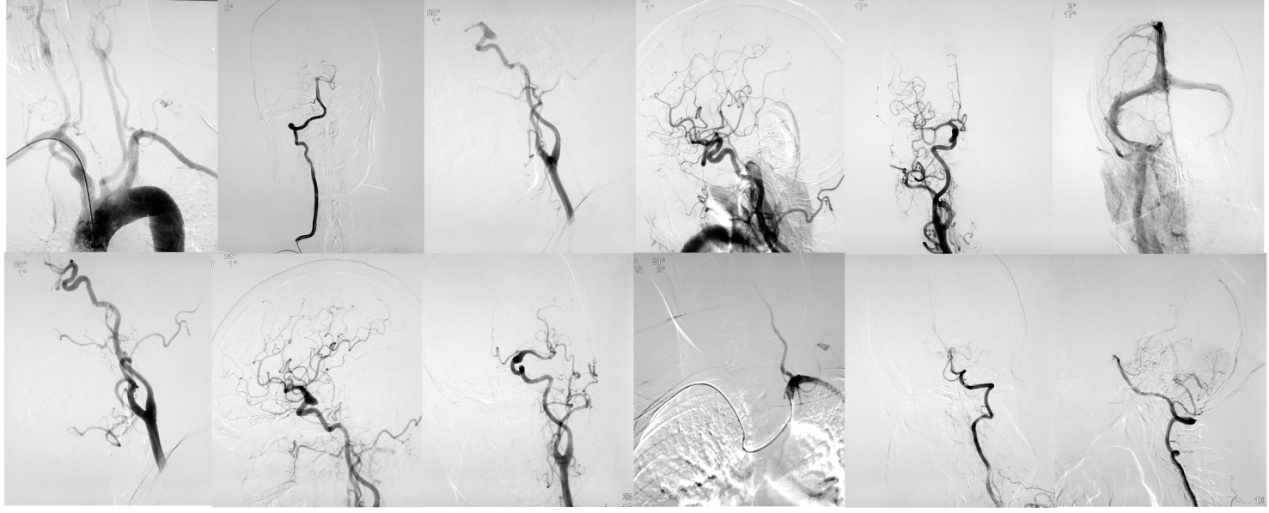

脑血管病是神经内科的第一大类疾病,具有高发病率、高致残率及高复发率的特点。在具有卒中高危因素的患者中提前发现血管病变而进行干预,是有效预防卒中发生的前提。数字减影全脑血管造影作为诊断脑血管病的金标准,在众多的检查手段中起着度量衡的作用。

改良导管分别对左、右侧颈总动脉及左、右侧椎动脉的超选示意图。